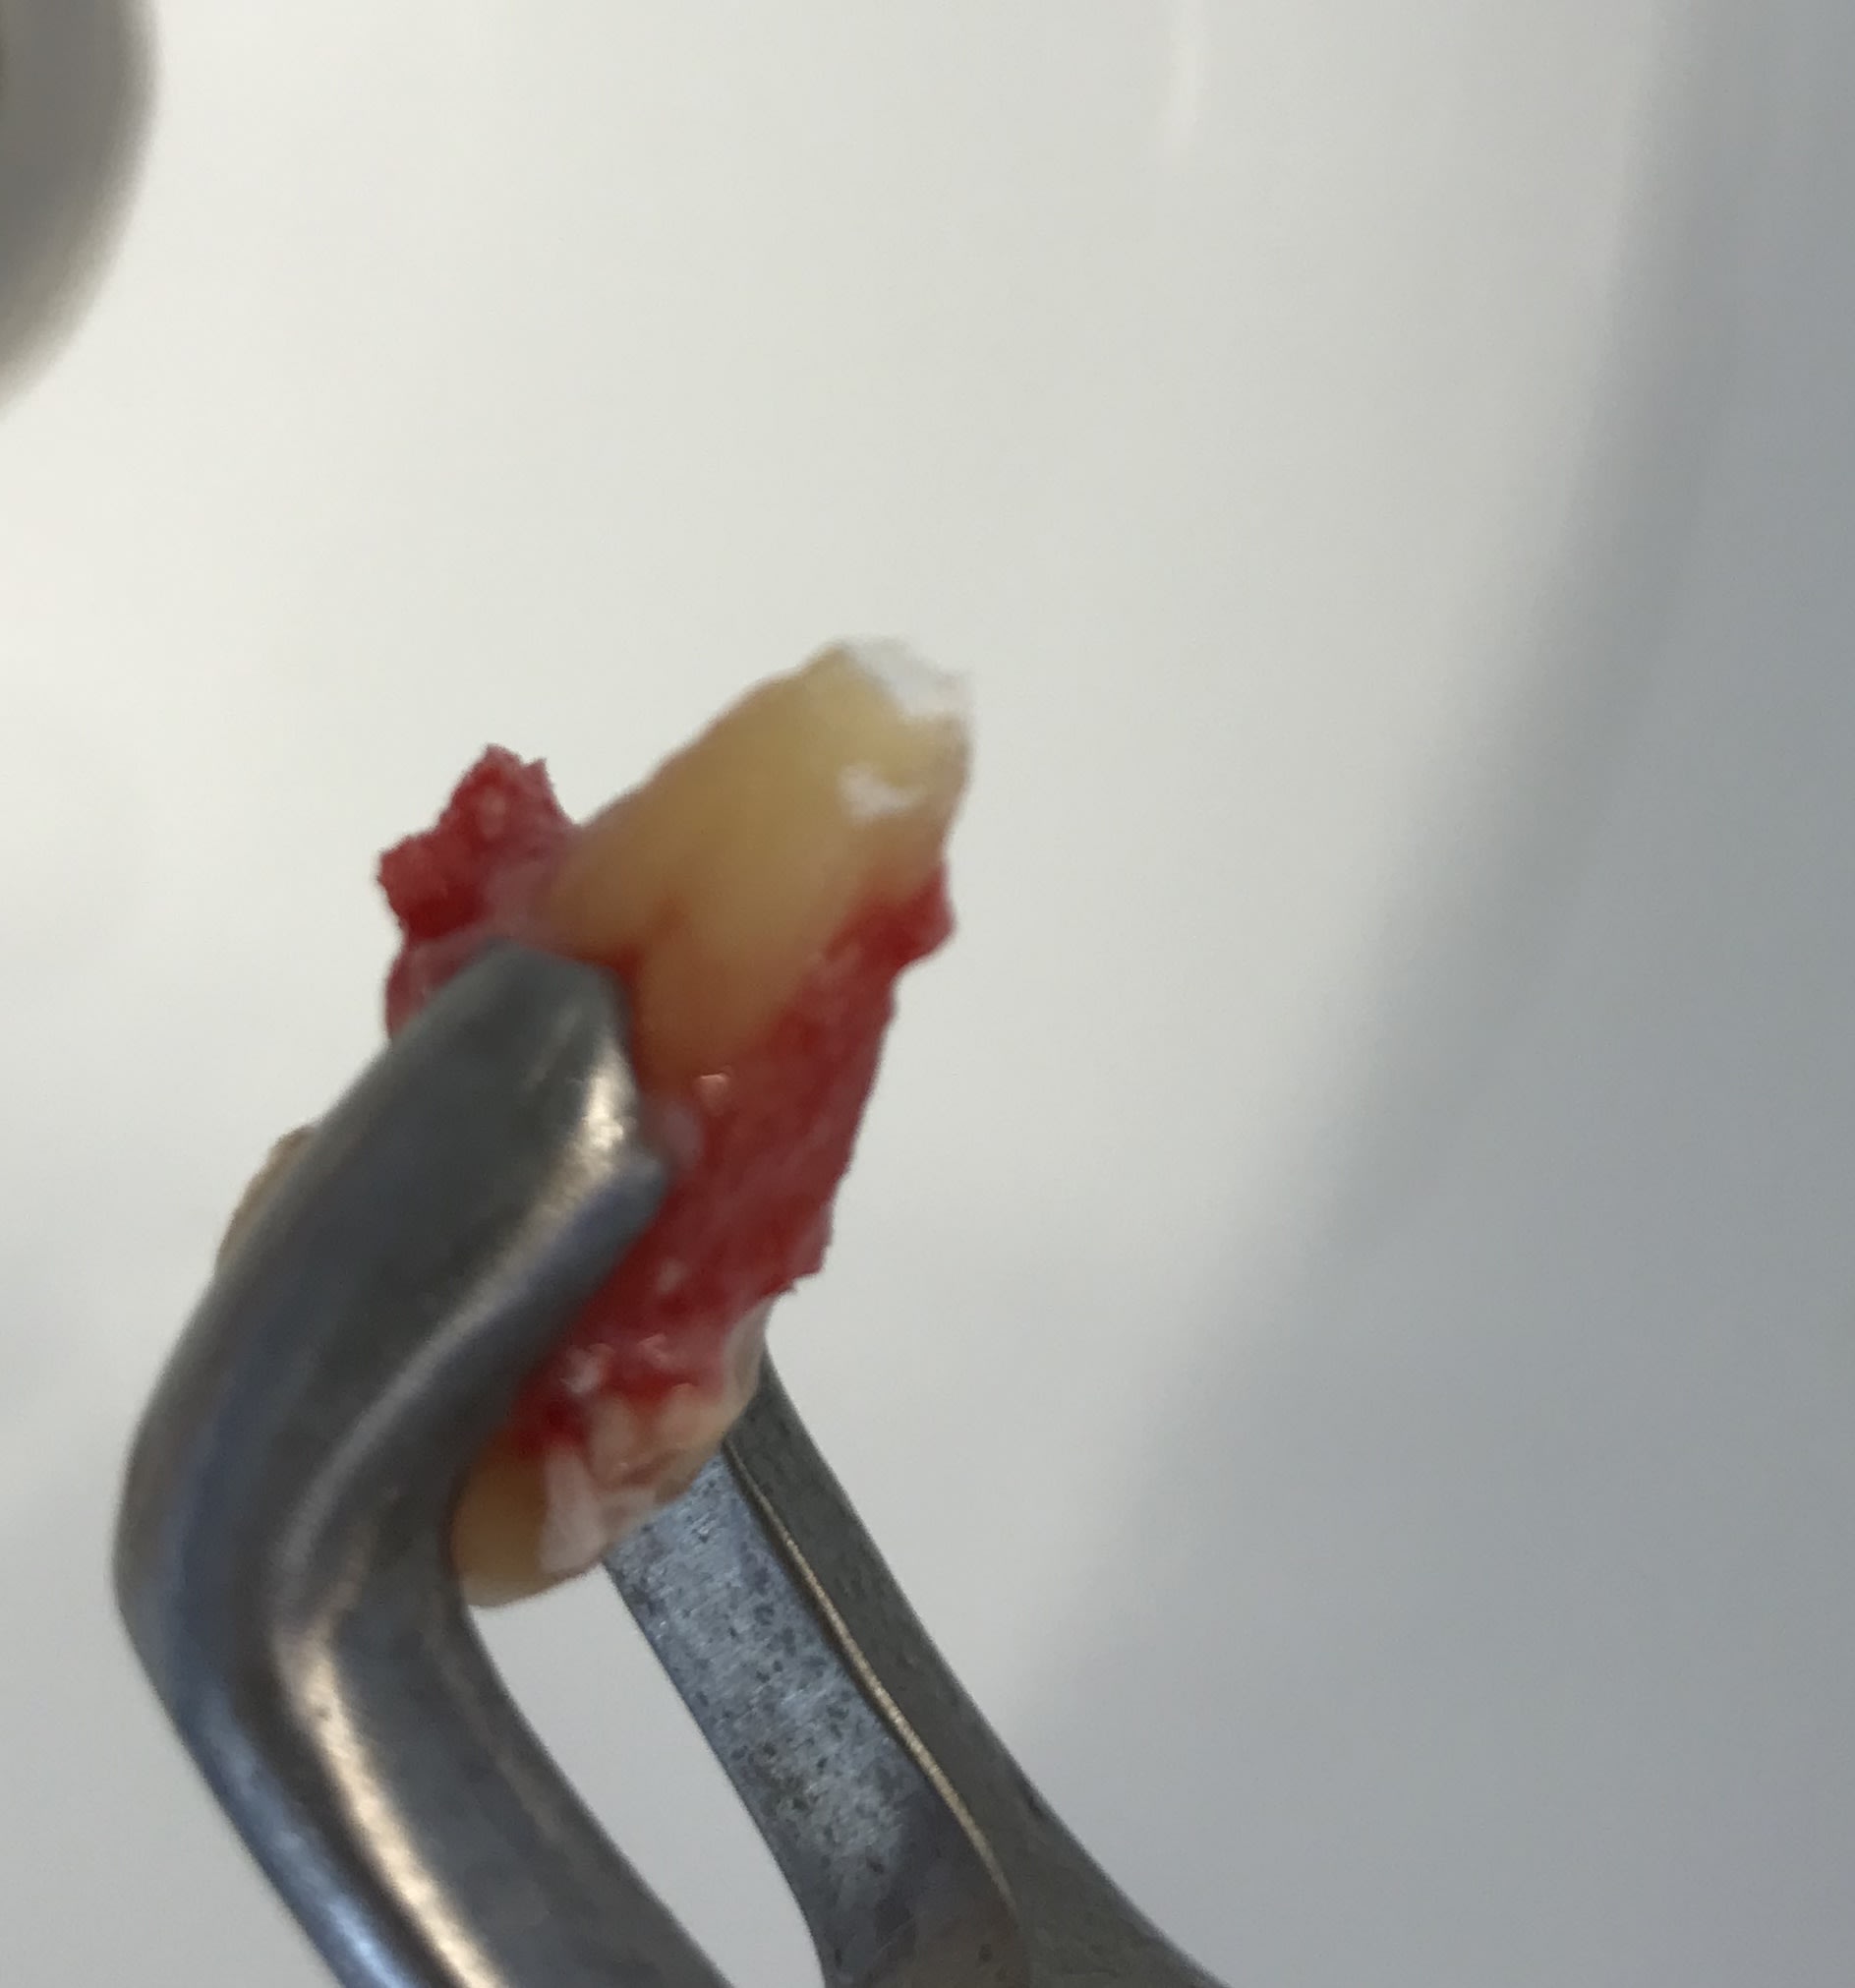

La première d’une série sur des indiens qui ont des pulpos sur molaires obturées avec Bakélite. Ils ont été sur le cul les indiens :)) extraction de la 48 curetage et ERI sur 47 et curetage

0638ebed ae87 40ce b05d bd6e9d3616a7 xkwc5o - Eugenol